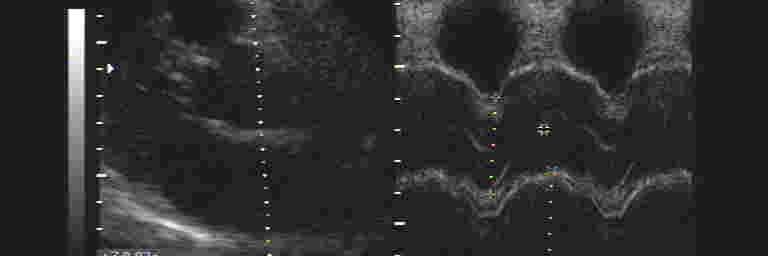

Herzecho (Farbdoppler-Echokardiographie)

Herzecho oder auch Echokardiographie bezeichnet man den Ultraschall vom Herzen. Hierbei kann festgestellt werden wie groß das Herz ist (Herzkammern und Vorhöfe), wie gut es sich kontrahiert (wie gut es "arbeitet" und pumpt) und ob alle Herzklappen funktionieren oder ob eine Herzklappe undicht oder aber zu eng ist.